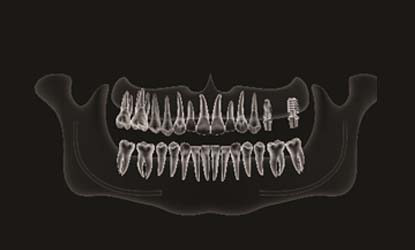

Problema: Trūksta krūminių dantų

Tikslas:

Pakeisti trūkstamus dantis dantų implantais

Rezultatas:

Atkurta pilnavertė kramtymo funkcija tvirtais ir patikimais fiksuotais protezais